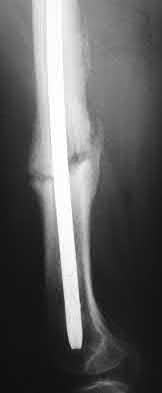

1. # A 32-year-old male sustains the injury shown in Figure A and undergoes treatment as shown in Figure B. Following placement of this implant, what is the best technique to confirm it is not too proud proximally?

1. Lateral radiograph of the knee

2. AP radiograph of the knee

3. Oblique radiographs of the knee

4. Merchant radiograph of the knee

5. Internally rotated 45 degree view of the knee Corrent answer: 1

The safe zone for tibial nail placement as seen on radiographs is just medial to the lateral tibial spine on the anteroposterior radiograph and immediately adjacent and anterior to the articular surface as visualized on the lateral radiograph.

Tornetta et al specifically located the safe zone for nail entry in a study using fresh frozen cadaver knees. The authors found that the safe zone for nail placement is located 9.1+/-5 millimeters lateral to the midline of the plateau and three millimeters lateral to the center of the tibial tubercle. The width of the safe zone averaged 22.9 millimeters and was as narrow as 12.6 millimeters.

The starting point of the of the nail can be best viewed on the lateral knee radiograph, an example of which is shown in Illustration A. Illustration B shows the "sweet spot" for nail insertion as defined by Tornetta.